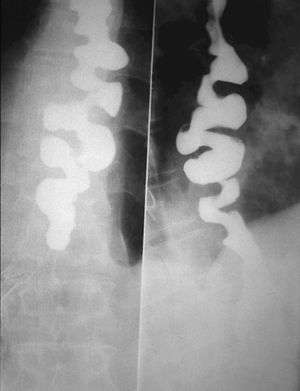

Corkscrew appearance of the esophagus.

Several radiographic findings are suggestive of DES, such as a "rosary bead esophagus" or "corkscrew" appearance on barium swallow x-ray, although these findings are not unique to DES.[1]